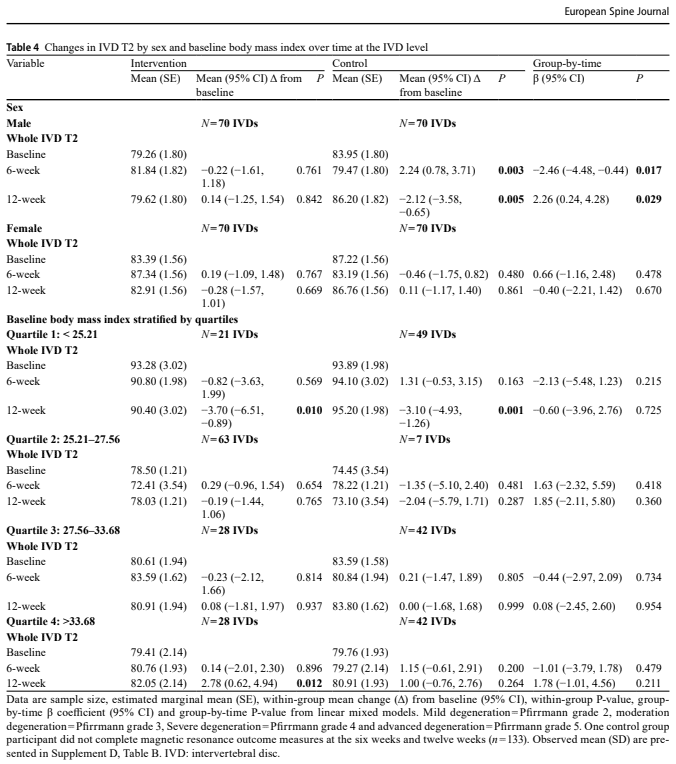

- Факторы пациента: Исходный уровень дегенерации (степень по Пфирману; суммарный балл по Пфирману), пол (мужской, женский) и индекс массы тела (ИМТ). Оценка по шкале Пфирмана - это система классификации для визуальной оценки степени дегенерации (IVD) с помощью МРТ. Она оценивает диски от одного (здоровые) до пяти (тяжелая дегенерация) на основании изменений в структуре IVD, различия между ядром и кольцом, яркости интенсивности сигнала и высоты диска. Оценка по шкале Пфирмана была одним из факторов пациента, использованных в исследовании для классификации исходного состояния IVD на подгруппы (нормальная, легкая, умеренная, тяжелая и прогрессирующая дегенерация) для анализа.

Анализ факторов пациента показал, что при стратификации IVD по исходному классу Пфирмана IVD с легкими дегенеративными изменениями отрицательно влияли на межгрупповые изменения Т2 IVD в течение 6 недель, но не в течение 12 недель.

Оказалось, что ИМТ не влияет на изменения в Т2 IVD ни в одной временной точке, что позволяет предположить, что масса тела может не оказывать существенного влияния на реакцию дисков на этот тип ступенчатой беговой нагрузки у лиц с ХЛБП. Это несколько удивительно, учитывая предыдущие данные, связывающие более высокий ИМТ с повышенной нагрузкой на позвоночник, и может указывать на то, что относительно низкие объемы бега в данном исследовании были недостаточны для выявления различий, связанных с ИМТ. Напротив, пол показал зависимый от времени умеренный эффект: мужчины продемонстрировали отрицательный эффект через 6 недель, но положительный эффект через 12 недель по сравнению с контрольной группой, в то время как женщины не показали значительного умеренного эффекта. Однако авторы отмечают, что ранние негативные изменения у мужчин, скорее всего, были обусловлены изменениями в контрольной группе, что позволяет предположить, что эти результаты отражают вариабельность, а не истинное физиологическое различие. Для клиницистов это означает, что реакция пола на нагрузку остается неясной и пока не должна определять различные рецепты упражнений, а ИМТ сам по себе не может быть ключевым фактором при назначении бега на низких и умеренных нагрузках для поддержания здоровья дисков.